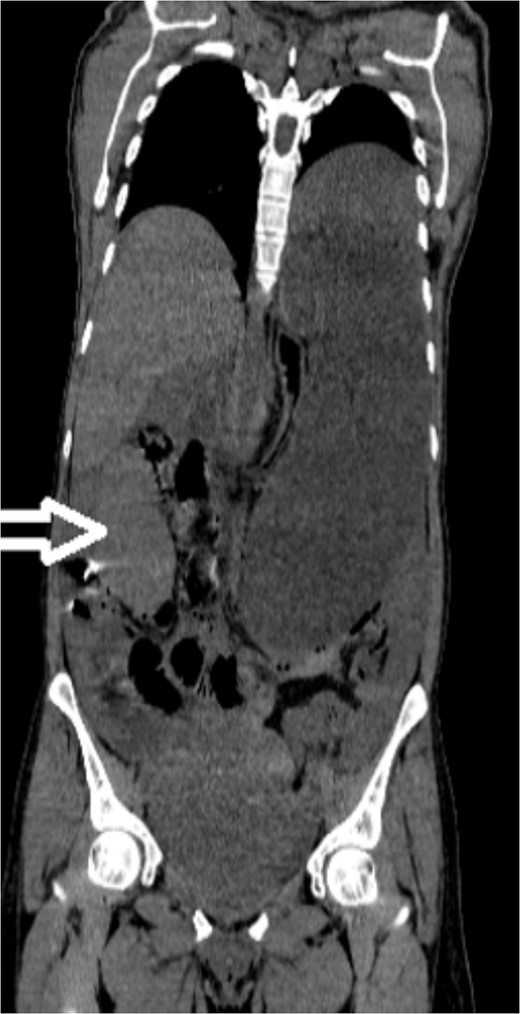

Upon admission to our hospital, the patient’s physical examination revealed hypotension (87/52 mmHg) and tachycardia (150 bpm), along with marked diffuse abdominal tenderness and guarding. Laboratory investigations indicated a hemoglobin level of 7.1 g/dl, a white blood cell count of 14.5 × 103 μl, and a platelet count of 202 × 103 μl. An abdominal CT scan without contrast showed an enlarged ectopic spleen measuring 18 cm in the right abdominal area, a distended stomach, a moderate volume of hemoperitoneum, and significant intra-abdominal fluid accumulation. CT findings are shown in Figs 1–3. Based on these findings, the patient was immediately transferred to the operating room.

Noncontrast axial CT scan of the abdomen showing a perihepatic hematoma.